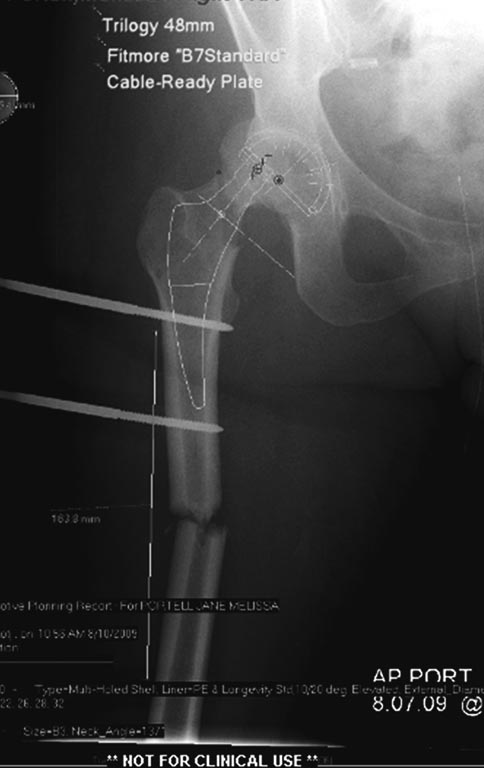

Из вариантов фиксации для проксимального и диафиза бедра выбрали пластину, а по поводу артропластики остается вопрос между тотальным или геми.

На всякий случай запланировали: короткий и длинный вариант ножки.

На 25 день с момента травмы операция на Jackson table с боковым обширным доступом. Удаление стержней с местной обработкой. В тазобедренном суставе удаление головки, на дне вертлужной впадины полная отслойка хряща. Вертлужный компонент с одним винтом и короткая ножка - Fitmore press fit stem. На второй день однократно доза радиации для профилактики гетеретопической оссификации. Послеоперационный период без температуры. Выписана. Нагрузку разрешили на левой стороне, а полная в 3 мес. Здесь снимки при амбулаторном наблюдении: послеоперационно, 2 мес, 3 мес и 6 мес. Нагрузка полная, отсутствует хромота, и нет жалоб.